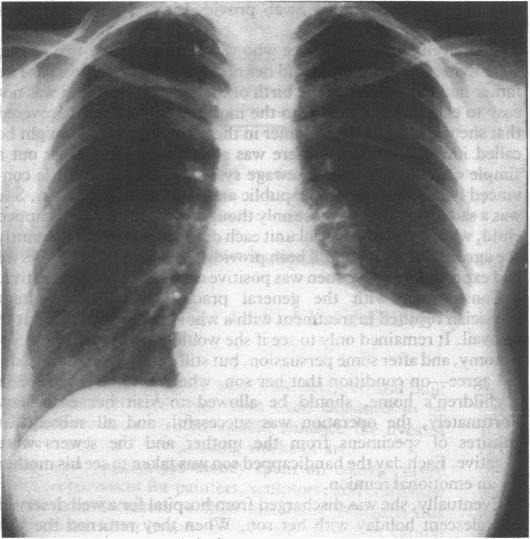

Lipoid pneumonia: an occupational hazard of fire eaters.

Br Med J (Clin Res Ed). 1984;289(6460):1728-9. doi: 10.1136/bmj.289.6460.1728.

https://cdn.ncbi.nlm.nih.gov/pmc/blobs/334f/1444802/4d378fbe2acf/bmjcred00533-0023-a.jpg

https://cdn.ncbi.nlm.nih.gov/pmc/blobs/334f/1444802/47d60c95efd5/bmjcred00533-0022-a.jpg